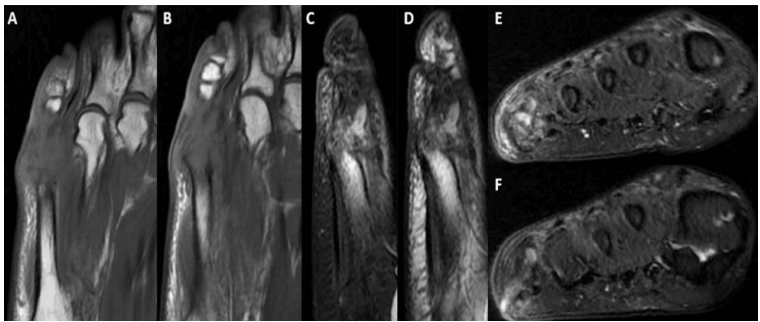

Figure 2: Initial MRI

Select T1 and T2 images from non-contrast MRI at 15 months demonstrating complete bony destruction of most of the proximal phalanx and metatarsal head.  Axial (A,B), Sagittal (C,D), Coronal (E,F). Note sinus tract on image F.

Due to poor patient compliance, further radiographs and the MRI were performed 15 months after the first presentation [figure 1 - 2]. These showed complete bony destruction of proximal phalanx and metatarsal head with a 2 x 1cm collection in the lateral soft tissue [figure 2]. During this period, her symptoms had continued to fluctuate with the use of multiple antibiotics, including flucloxacillin, ciprofloxacin, metronidazole, co-trimoxazole and clarithromycin. The end result was the development of a discharging sinus, persistent swelling, localised erythema and pain. A month later a contrast MRI was performed to further delineate the lesion, which demonstrated no collection and a sinus tract in keeping with chronic infection [figure 3]. At three years following initial presentation, the symptoms worsened and the patient consented to surgical treatment consisting of amputation of the fifth toe at the level of the distal meta-diaphysis of the fifth metatarsal.